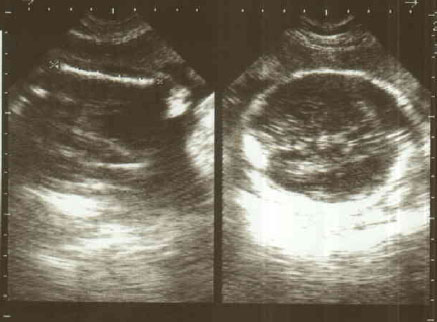

Attachment 3132

Attachment 3133